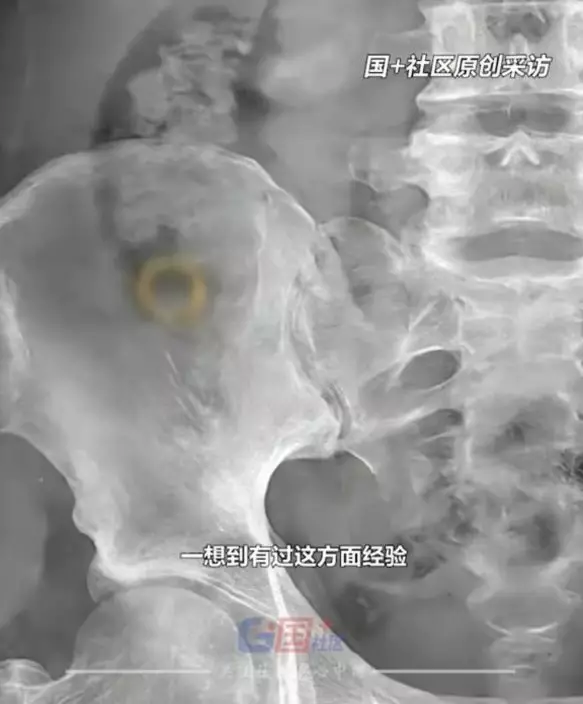

醫生進行X光檢查後,清楚看到金戒指停留在胃部位置。由於妻子並無出現腹痛或其他不適症狀,醫生評估暫毋須手術處理,建議回家觀察待自然排出。儘管如此,男子仍為此整晚忐忑不安。